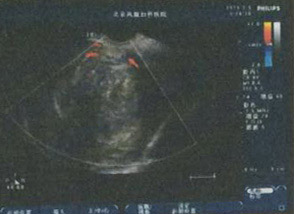

- 彩超及子宫输卵管造影发现其子宫内 8.2cm*6.8cm巨大肌瘤

德国WOLF宫腹腔镜检查

发现“8.2cm*6.8cm”巨大肌瘤

发现“8.2cm*6.8cm”巨大肌瘤

董长江教授耐心接待并做了详细检查,彩超、子宫输卵管造影及宫腹腔镜检查,发现其子宫内8.2cm*6.8cm巨大肌瘤,被确认为:宫内低回声子宫肌瘤。

- 专业彩超及宫腹腔镜检查发现巨大肌瘤